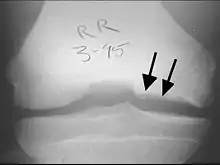

X-rays show lucency of the ossification on the anterior aspect of the knee in juvenile patients. In older people, the lesion typically appears as an area of osteosclerotic bone with a radiolucent line between the osteochondral defect and the epiphysis. The visibility of the lesion depends on its location and on the amount of knee flexion used. Harding described the lateral X-ray as a method to identify the site of an OCD lesion.[36]

CT scan and projectional radiography of a case of osteochondritis dissecans of parts of the superio-medial talus.